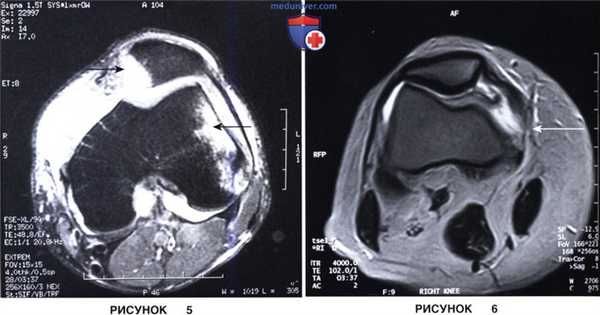

в) Магнитно-резонансная томография (МРТ) является наиболее информативным методом, позволяющим обнаружить участки отека костного мозга, локализовать разрыв МБНС, диагностировать хондральные повреждения, сопутствующие повреждения менисков и связок коленного сустава:

• На рис. 5 представлена Т2-взвешенная МР-томограмма с классическими костными изменениями в виде отека костного мозга наружного мыщелка бедра и медиальной фасетки надколенника

• На аксиальной МР-томограмме (рис. 6) видны признаки отрыва МБНС в области ее прикрепления к бедренной кости.